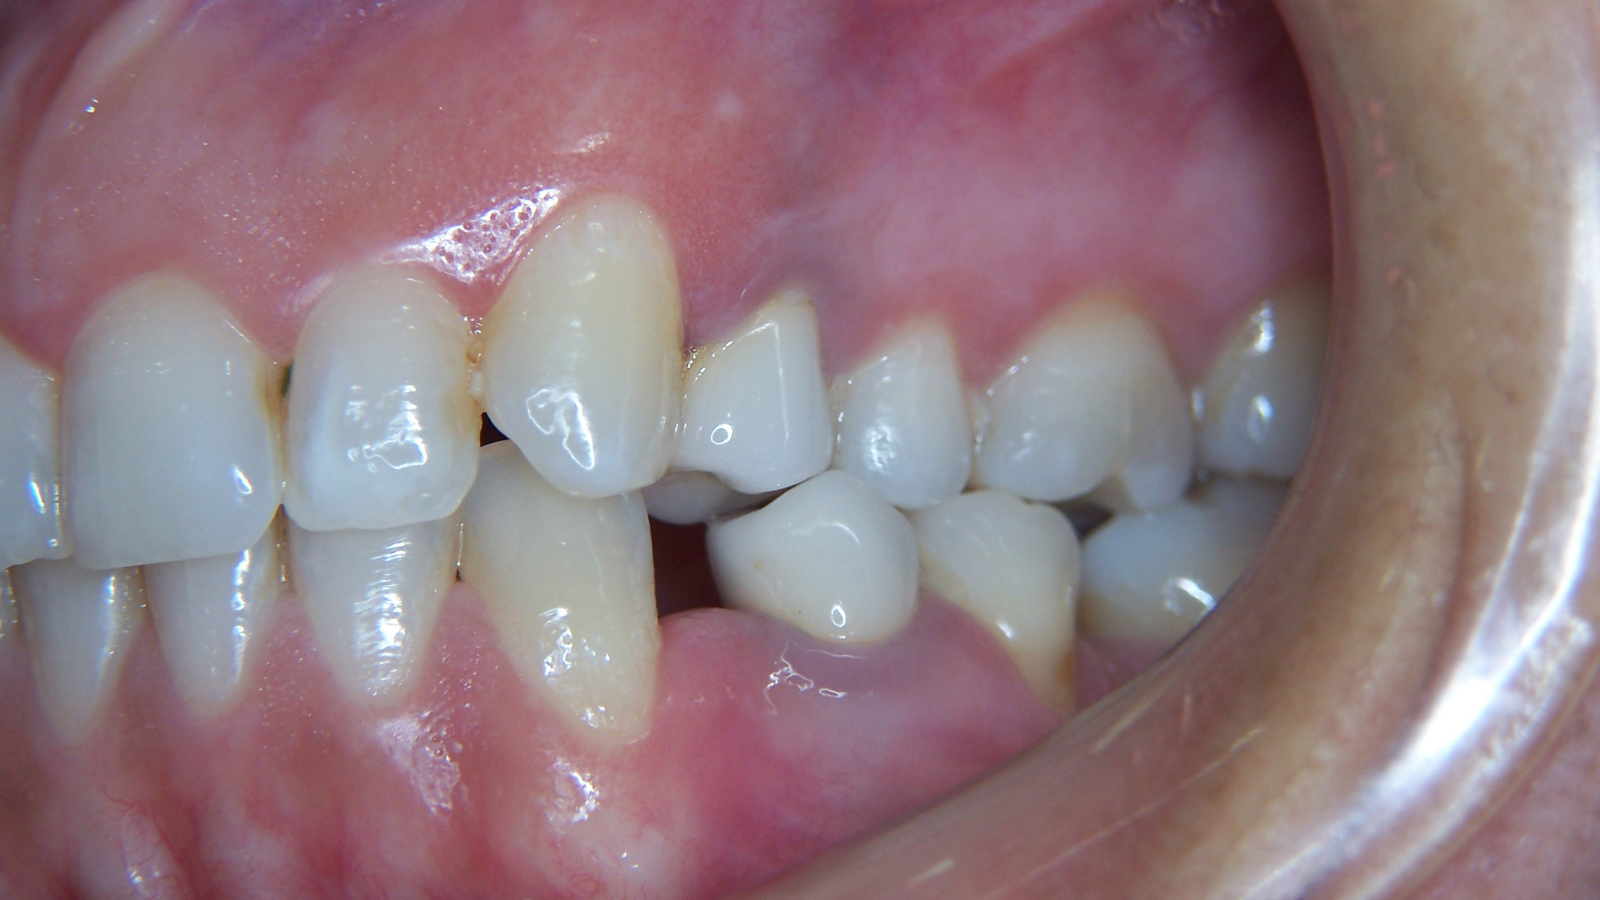

Une jeune patiente arrive en fin de traitement orthodontique pour un déficit esthétique.

La difficulté réside dans la réalisation de prothèses différentes dans le même secteur : jongler avec la full-zircone et le disilicate de lithium.

Ce challenge fut le sujet de mon mémoire du DU d’esthétique de Strasbourg en 2008.

L’expérience et l’investissement dans le digital depuis 2017 rendent le résultat plus prévisible.